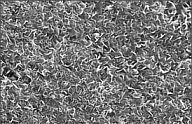

SEM picture |

SEM picture ( x3,500 )

Ca-P thin film-coated

surface |

arrow

head: resorption pit /arrow:

osteoclast |